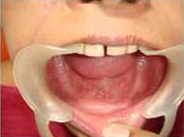

GTR Membrane on Bone Graft

Use of Bone Graft & GTR membrane for an Implant

Suturing after Bone Grafting